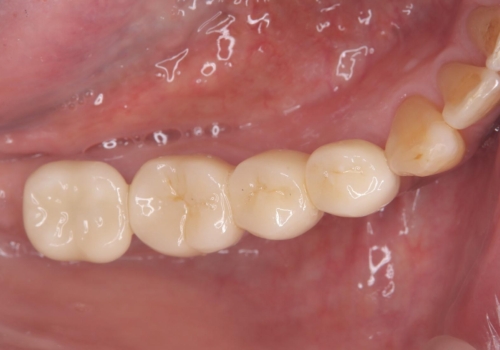

被せ物がとれた オールセラミックによるブリッジ治療

コアごと脱離して来院し、フェルールの獲得が厳しいためコアが立てられないので抜歯することになりました。

インプラントとブリッジの治療を提案し早く噛めるようにしてほしいという要望があったためブリッジにて治療をすることになりました。